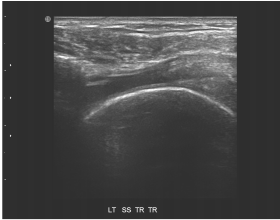

72.

85歲女性患者,主訴左肩疼痛超過6個月,有局部壓痛,無肌肉萎縮現象,圖為左肩部超音波檢查,上圖為旋轉環帶長軸切 面,下圖為短軸切面,最可能之診斷為何? (A)風濕性關節炎(rheumatoid arthritis) (B)棘上肌腱斷裂(supraspinatus tendon tear) (C)化膿性關節炎(pyogenic arthritis) (D)肩三角肌撕裂(deltoid muscle tear)